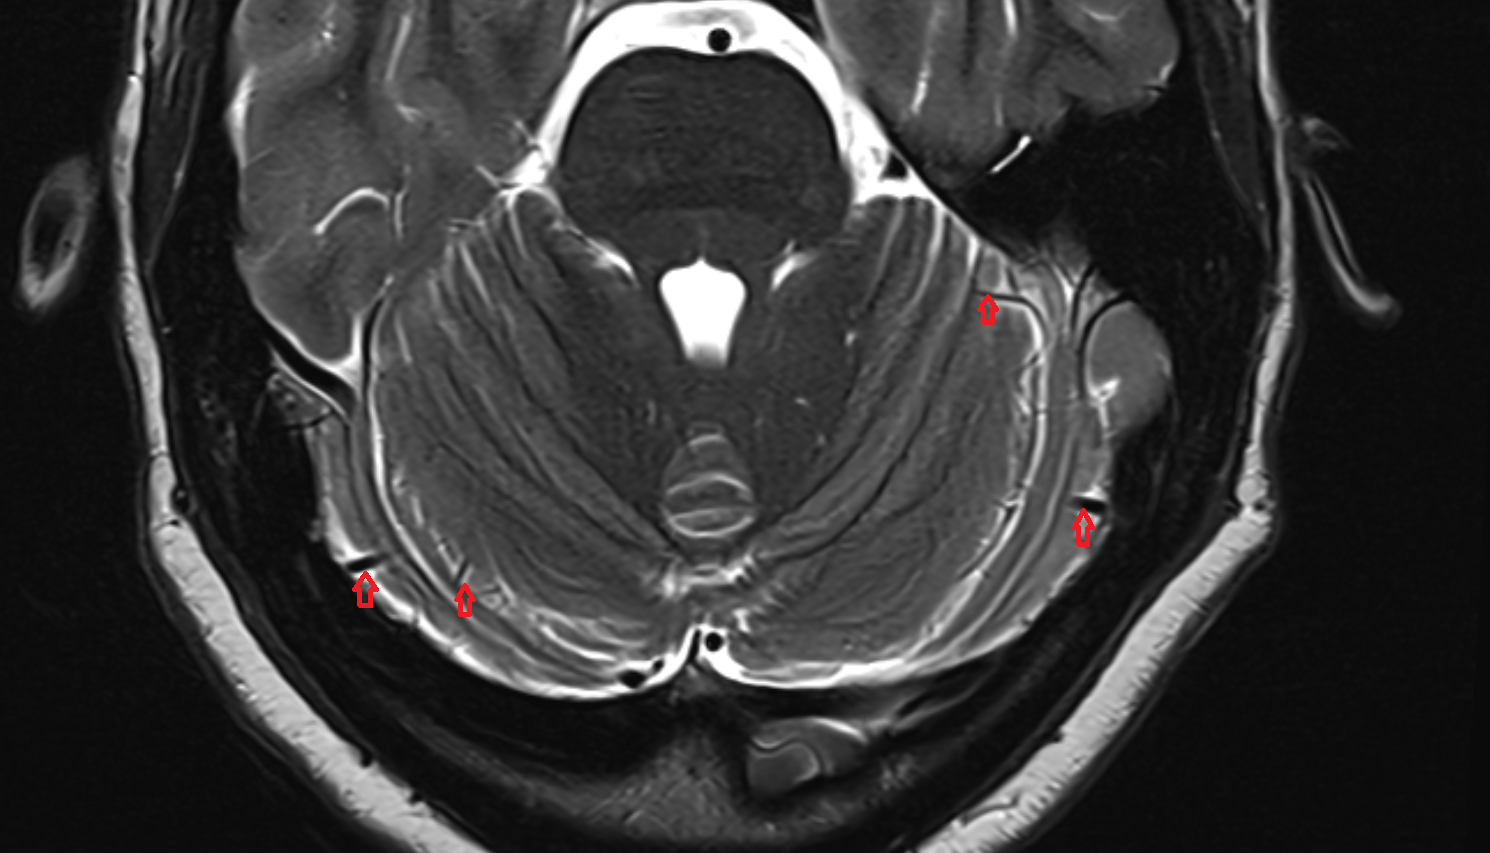

- Cerebellum